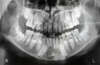

L’extraction d’une dent est toujours précédée d’un questionnaire (recherche de risques hémorragiques) et d’une radiographie.

Cet examen radiologique permettra de déterminer s’il faut procéder à une extraction simple ou à une extraction chirurgicale.